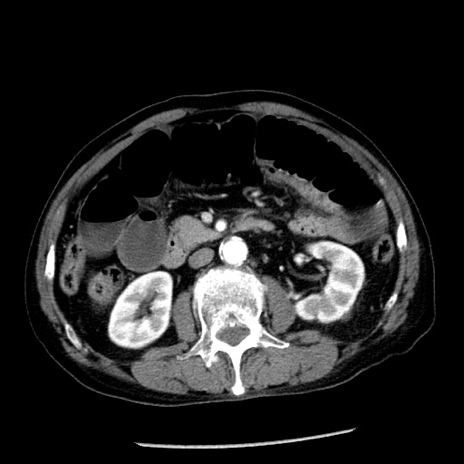

冠状断像

症例26(横断像)

【症例】80歳代男性

【主訴】嘔吐

【現病歴】昨晩2回嘔吐あり、今朝になっても嘔吐あり。来院。

【既往歴】胃潰瘍

【身体所見】意識清明、BT 37.6℃、BP 166/95mmHg、HR 100bpm、SpO2 97%、腹部:平坦・軟、腸蠕動音聴取良好、圧痛なし。

【データ】WBC 21900、CRP 1.46